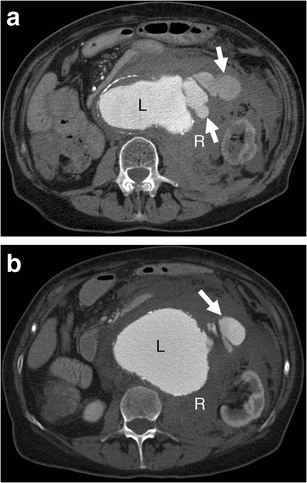

Contrast extravasation

Contrast extravasation. a-b Axial enhanced CT of a 75-year-old woman demonstrates active contrast extravasation (white arrows) from the aneurysm lumen (L) into the retroperitoneal space with massive retroperitoneal haematoma (R)